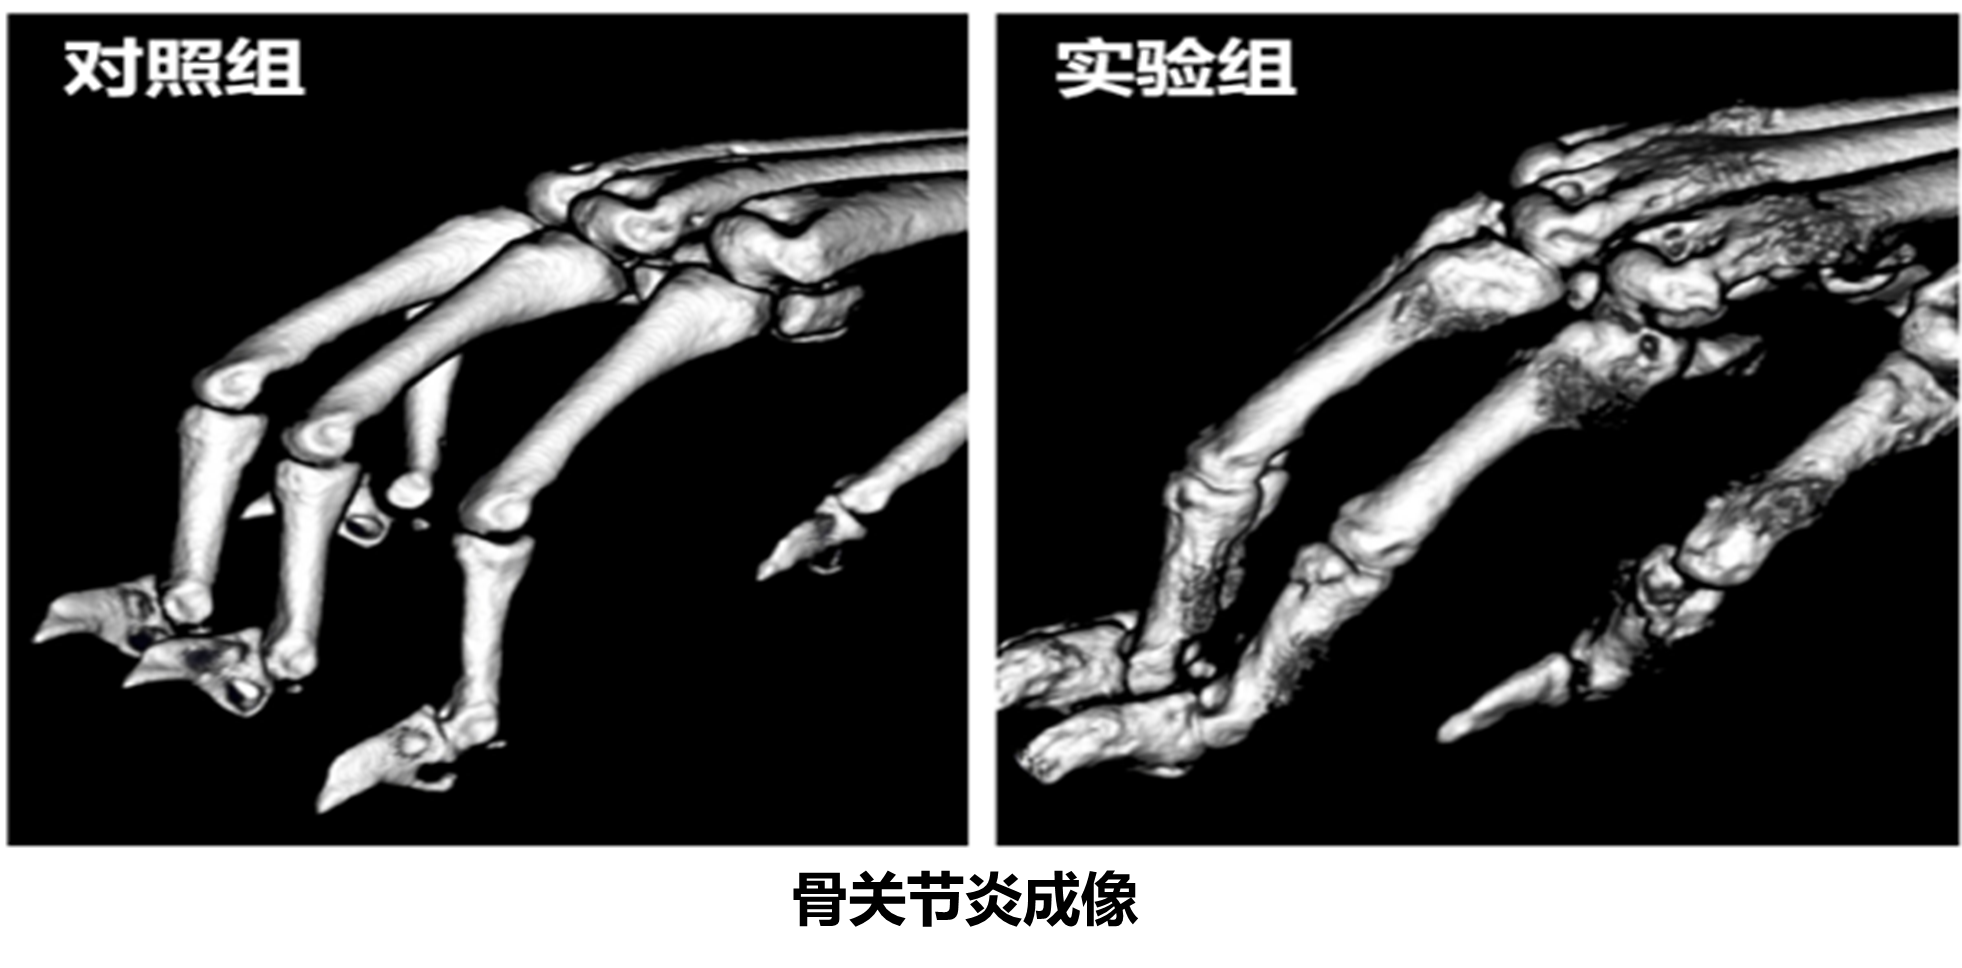

该设备支撑高等医学研究院、基础医学院、口腔学院、齐鲁医院等学院及附属医院在口腔、骨骼、心血管、肿瘤等方面高效开展科学研究;助力“胃肠道间质瘤治疗的脂肪酸和类固醇膜受体的靶点发现、功能研究及靶向药物的发展”等多项国家自然科学基金项目落地;支撑十余篇科研文章在《Science Advances》、《Cell Death &Disease》、《Molecular Pharmaceutics》等高水平学术期刊上发表。